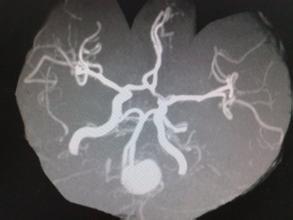

2.CT掃描

通常腦幹膠質細胞瘤以低密度灶和腦幹腫脹多見,少數呈等密度或稍高密度影,囊變甚少;向上可侵及視丘,向後外可發展至腦橋臂及小腦半球。強化掃描可有不均勻增強或環形增強。海綿狀血管瘤在出血的急性期為均勻的高密度;在亞急性及慢性期為低密度。室管膜瘤為高密度,能增強。血管網狀細胞瘤為高密度,顯著增強。結核球呈環形高密度,中央為低密度,能顯著加強。為區別腦幹腫瘤和腦幹外腫瘤,必要時可進行腦池造影CT掃描。CT掃描可將腦幹腫瘤分為3型:Ⅰ型為無強化病灶,表現為低密度病變;Ⅱ型瀰漫性強化;Ⅲ型為環形強化。其中Ⅰ型多見,Ⅱ、Ⅲ型較少見。